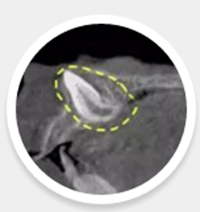

用上我們的超級武器——CBCT:一切無所遁形。

2.png

右上門牙恒牙胚旋轉著埋在鼻底,牙根變短且彎曲,根尖口已經(jīng)閉合,畸形嚴重!

由于外傷導致恒牙胚牙根過短且彎曲,這種牙齒即使牽引萌出,生存質量也很差,保留意義不大,所以只能很遺憾地選擇拔除了。